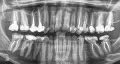

Уже вот месяц мучаюсь с зубами. Боль появляется ближе к обеду. Болит 4-ка снизу слева, и вот спустя месяц болит уже вся челюсть. До этого никогда не болели зубы, поэтому не могу определить ― зубы это или же десна. У врачей была, в нескольких клиниках, говорят ― зубы и десна полностью здоровые.

Болит в основном особенно 4 снизу, когда сжимаю челюсть или нажимаю на зуб. Кажется, что зубы с левой стороны стали чуть-чуть шататься.

Хочу сказать, что Вы запустили вашу 4-ку. Болит именно он, его надо лечить пока не поздно. От него все вокруг болит. Возможно, что за месяц он уже в таком состоянии, что спасти его не удастся, потому что по Вашему описанию процесс воспаления затронул кость вокруг корня этого зуба.

Не затягивайте дальше, уже скоро появится припухлость, разовьется периостит и неминуемое удаление зуба.